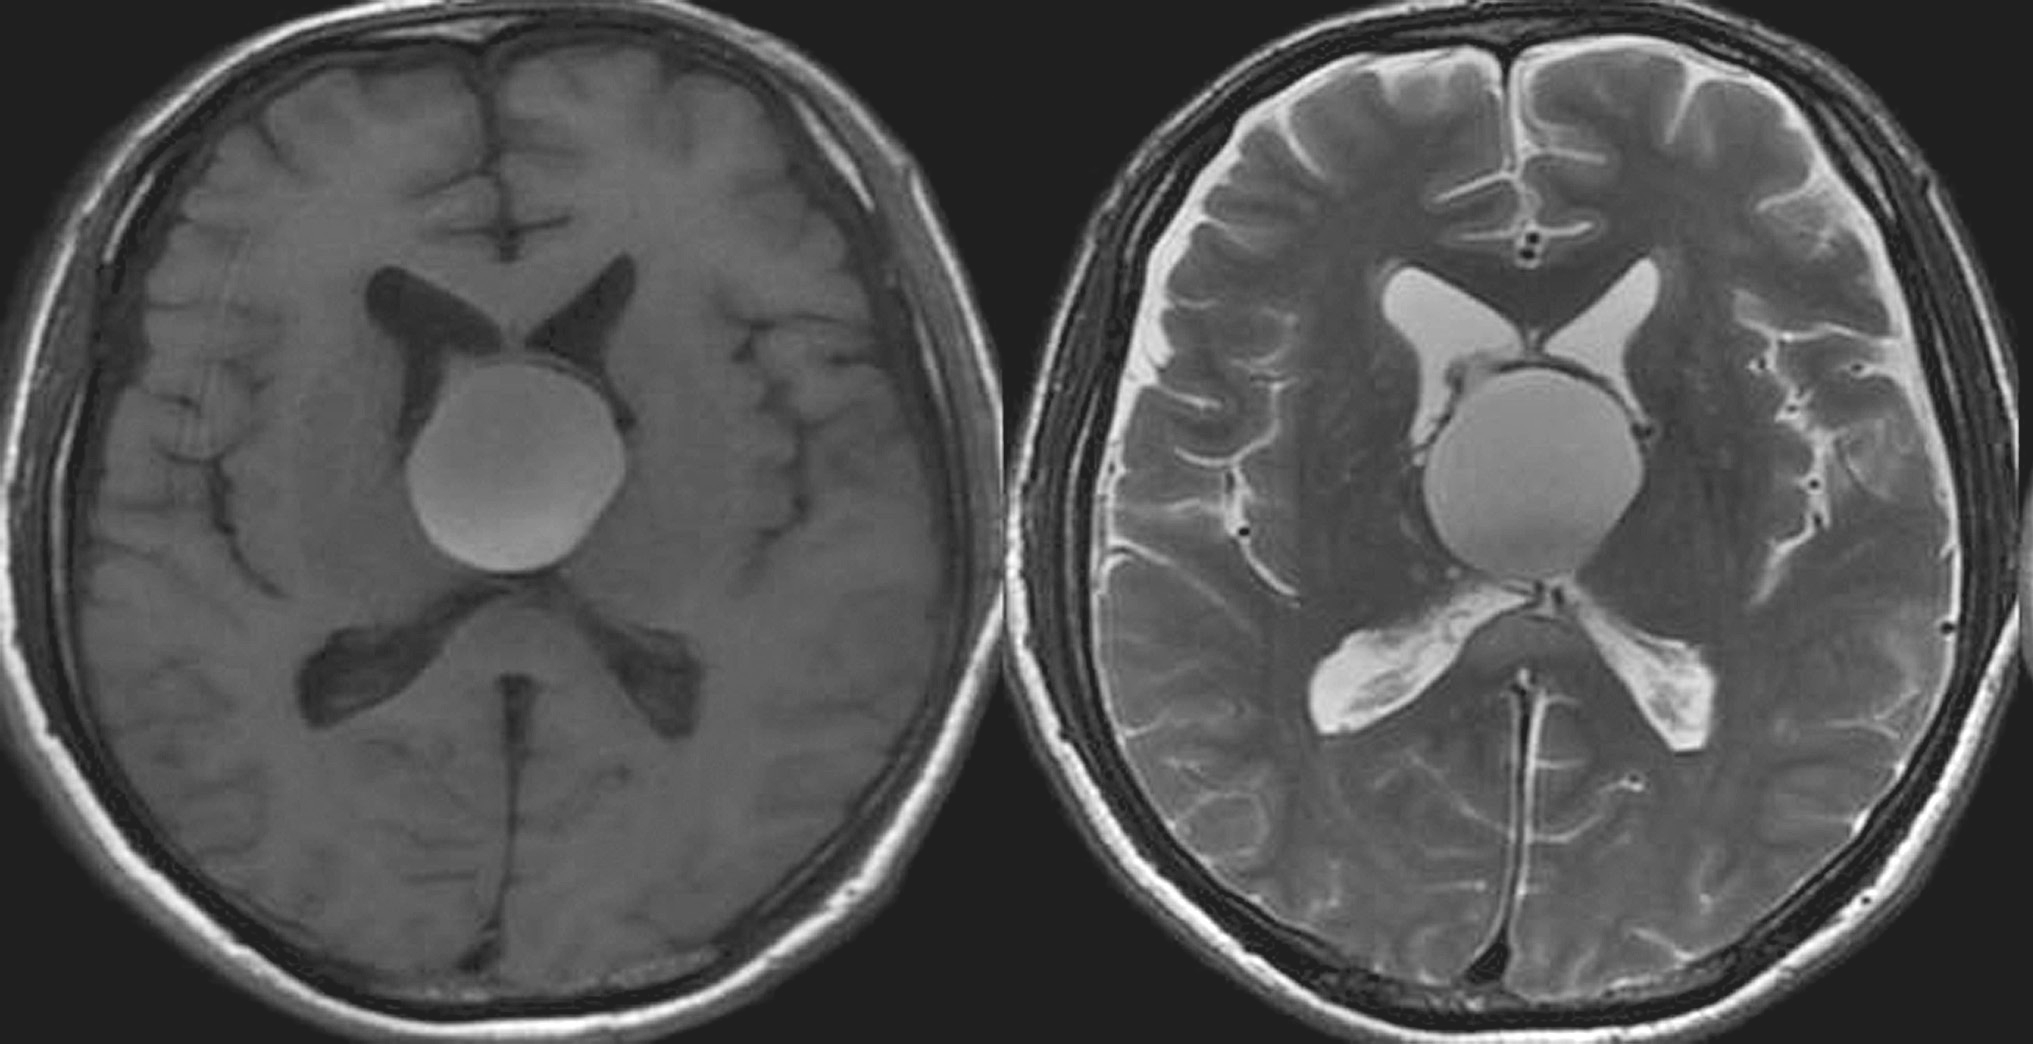

(2)MRI表现(图5-1-2):

①脑室系统明显扩大,蛛网膜下腔消失;②脑室额角和/或颞角呈圆形,伴脑室周围呈低或等T 1 信号、高T 2 信号的间质性水肿带;③第三脑室呈球形扩大,视隐窝和漏斗隐窝变浅变钝;④胼胝体位置抬高。

图5-1-2 高压力性脑积水的MRI表现

术后查体:神志恍惚,能简单回答问话。双瞳孔等大正圆,直径4.0mm,对光反射灵敏。颈软。四肢自主活动良好,肌张力略高。双侧Babinski征阴性。给予抗炎、脱水及对症治疗。术后24小时内复查头颅CT结果显示脑室系统明显变小(图5-1-4)。术后第3日患者神志清楚,问答合理。双侧脑室引流管通畅。术后第4日完善头颅MRI检查(图5-1-5)。双侧侧脑室外引流术后第6日于全身麻醉下行“经纵裂-胼胝体-穹窿间入路第三脑室内占位病变切除术”。手术过程顺利,复查头颅CT显示完全切除肿瘤,脑室大小基本正常(图5-1-6)。病理检查结果回报:胶样囊肿。患者2周后出院。目前随访恢复良好,未见肿瘤和脑积水复发。

图5-1-5 脑室外引流术后MRI表现(引流术后第4日)